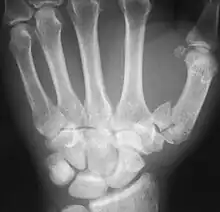

Fractures

Fractures to metacarpal bones account for 30-40% of all hand fractures, of which 25% occur in the first metacarpal (second to fractures to the fifth metacarpal bone). 80% of fractures to the first metacarpal occur at its base. [6]

Common fractures to the thumb metacarpal include Bennett's fracture and Rolando's fracture

Fracture of the first metacarpal (Rolando's fracture).